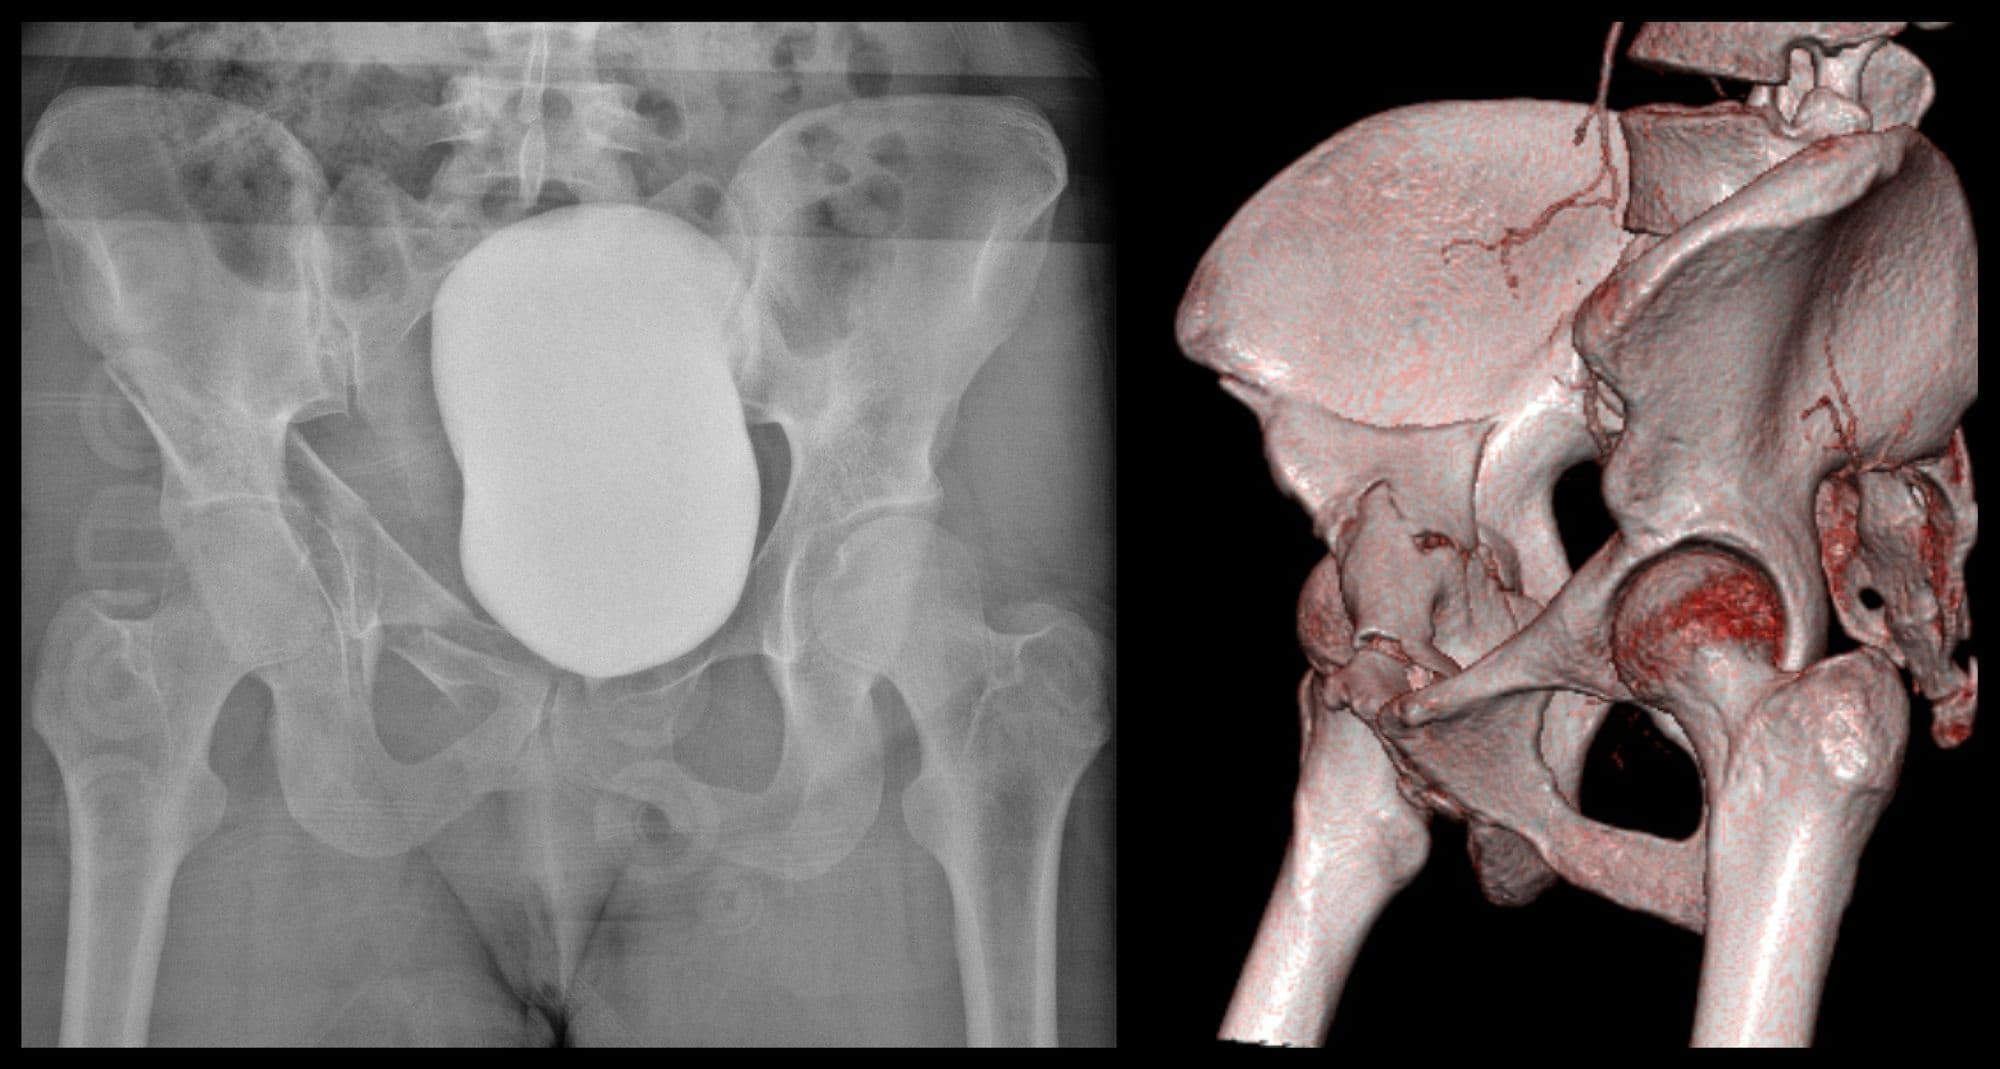

Posterior Sacroiliac Joint Fixation